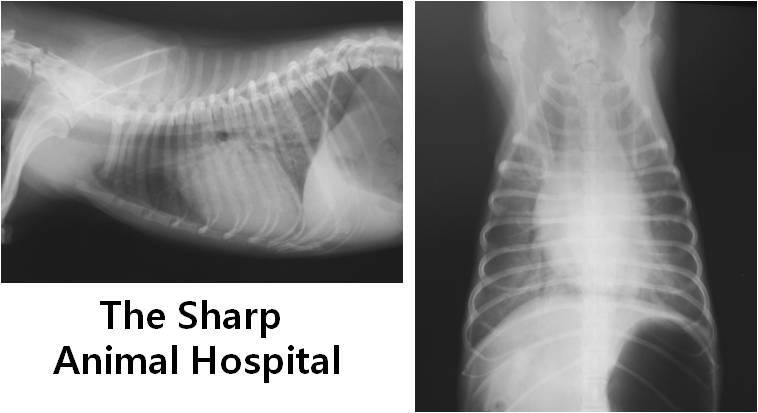

일단 먼서 나이 상으로 가장 의심되는 것이 심장 질환이기 때문에

심음 청진과 함께 흉부 방사선 검사를 실시 하게 되었습니다.

이러한 심청진 으로 심장의 이상을 의심하며, 흉부 방사선을 촬영 하였는데

폐 뒤 쪽으로 심하게 폐 수종이 관찰이 되었습니다.